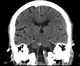

Tortuous vertebral artery

The posterior spinal artery (dorsal spinal arteries) arises from the vertebral artery in 25% of humans or the posterior inferior cerebellar artery in 75% of humans, adjacent to the medulla oblongata. It supplies the grey and white posterior columns of the spinal cord. [Source: Wikipedia ]